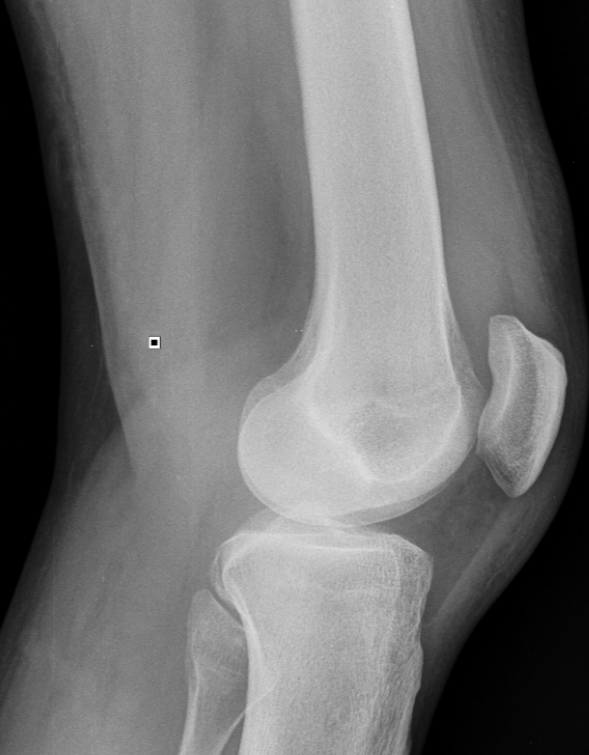

3. Suprapatellar effusion